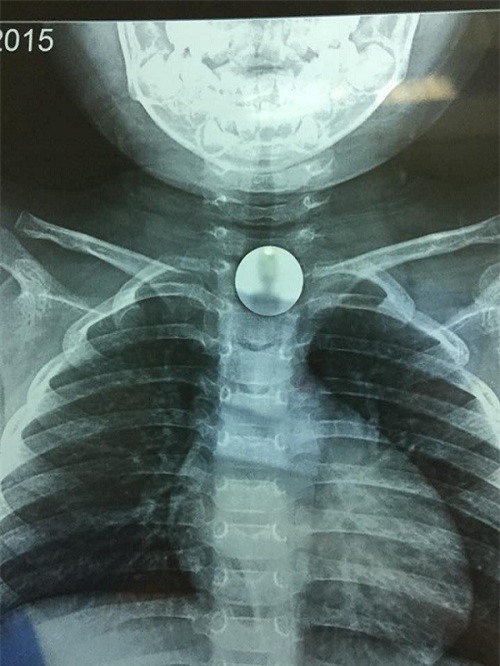

(DNVN) - Trong lúc đùa nghịch, bé gái N.H.N.K (3 tuổi, Long Biên, Hà Nội) không may nuốt đồng xu vào cổ họng, bệnh nhi được cấp cứu tại Bệnh viện đa khoa Đức Giang (Hà Nội).